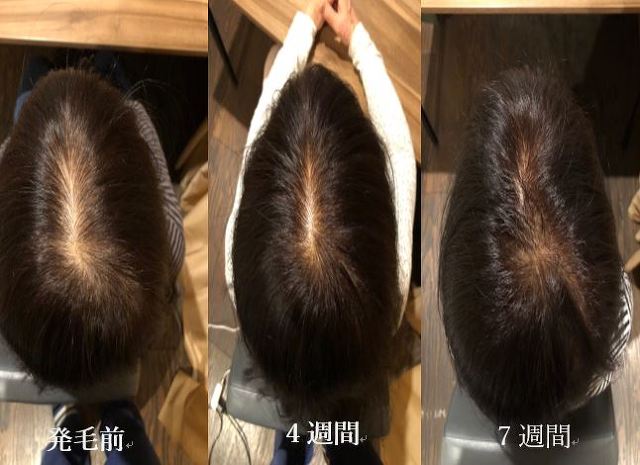

★発毛・薄毛部門からのお知らせ★

⚡薄毛・育毛にお困りの方に朗報です⚡

☑市販の育毛剤じゃ効果が出ない

☑抜け毛が気になってきた

☑全体的に髪のボリュームがなくなってきた

☑親族に薄毛の方がいる

こんな方はぜひご相談ください!

確実に満足のいく結果を出します!

嬉しいお知らせ!初回のカウンセリングは無料です。

完全予約制なので貸切でご相談いただけますので内容を聞かれる心配もなし!

あなたにとって「人生最後の発毛治療」にしましょう。

本気で私もあなたと向き合います!

「発毛のカウンセリングをお願い!」とご連絡下さい。

発毛専用ページ⇒https://peraichi.com/landing_pages/view/boubou1991

※「臍帯幹細胞の薄毛治療カウンセリングを受けたい」

とご連絡ください!

当院の発毛治療はオンラインでも対応しております。